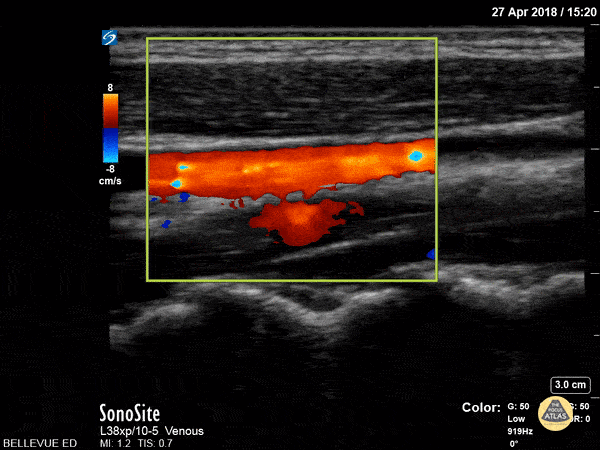

In this clip the probe sweeps between the internal jugular vein (red, demonstrating respiratory variation) and the common carotid (blue, pulsatile) in long axis with color doppler overlay. Hannah Kopinksi and Dr. Lindsay Davis - NYU Emergency Medicine